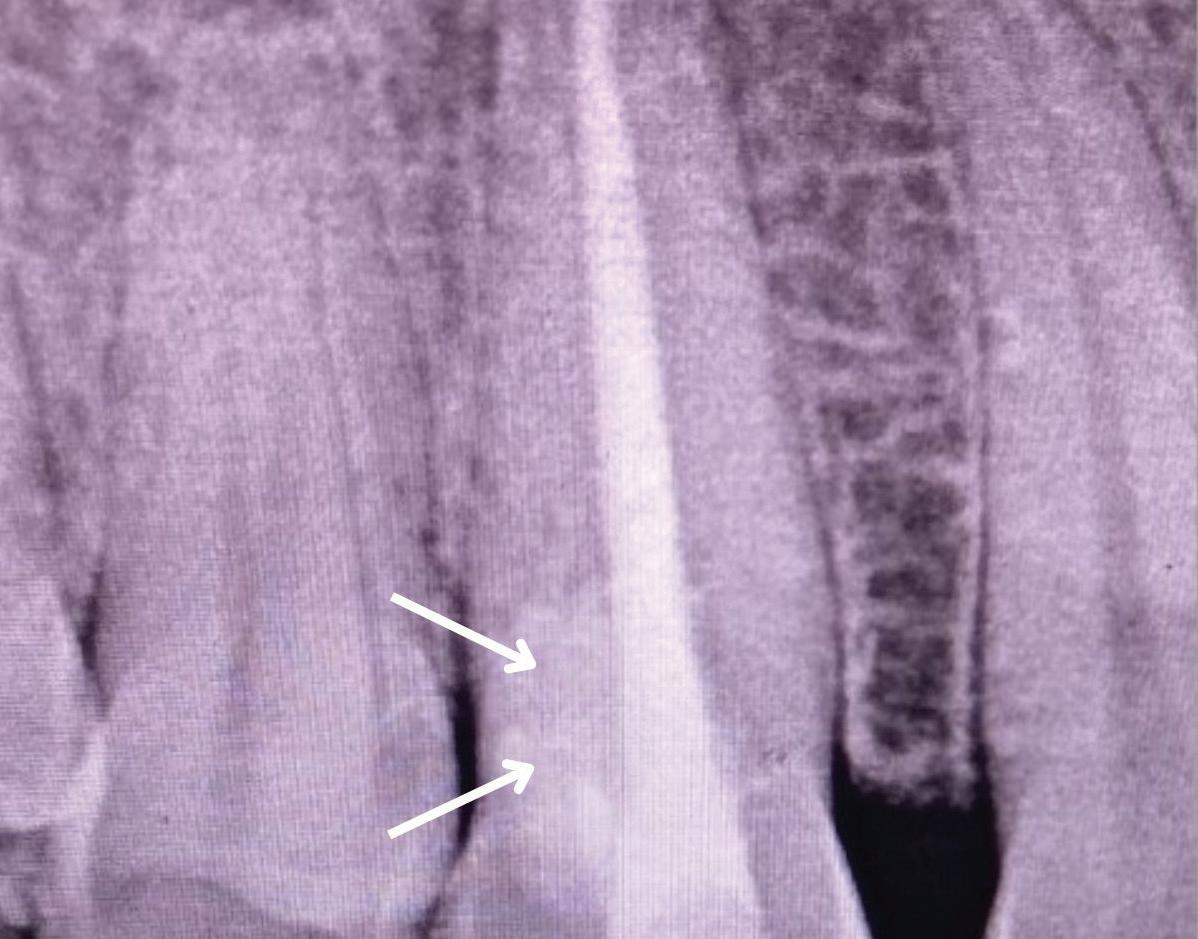

Fig 1. Microscopic visualization of the radicular extension of the crack (arrows) entering the canal.

Fig 2. Gutta percha removed 2 mm apical to the terminus of the fracture (arrows).

In the endodontic stage, conservative endodontic preparation and obturation with modern techniques are performed as they are for any tooth. All endodontic procedures are performed under an operating microscope to maximize visualization and illumination of the fracture line (Fig 1). The coronal portion of the newly placed gutta percha is removed 2 to 3 mm below the deepest extent of the crack in the affected canal to prepare for intraradicular barrier placement (Fig 2). Gutta percha is also removed 2 to 3 mm into the other noncracked canal orifices in the tooth to prepare for traditional orifice barriers. Microscopic transillumination with a fiber-optic light, in which an LED light probe is placed against buccal or lingual tissues overlying the roots, is utilized to illuminate the root and enhance visualization of the crack (Fig 3). A flowable resin-modified glassionomer or composite resin is then placed in this newly created void from the level of the gutta percha to the floor of the pulp chamber in all canal orifices (Fig 4). A composite resin core is then placed to permanently restore the endodontic access. If a temporary or permanent crown is not placed immediately after the endodontic procedures, the tooth is reduced

Periapical radiograph at the completion of the endodontic protocol. Resin-modified glass ionomer cement is placed as an intraradicular barrier in the distal canal, along the pulpal floor, and as an orifice barrier in the mesial canals.